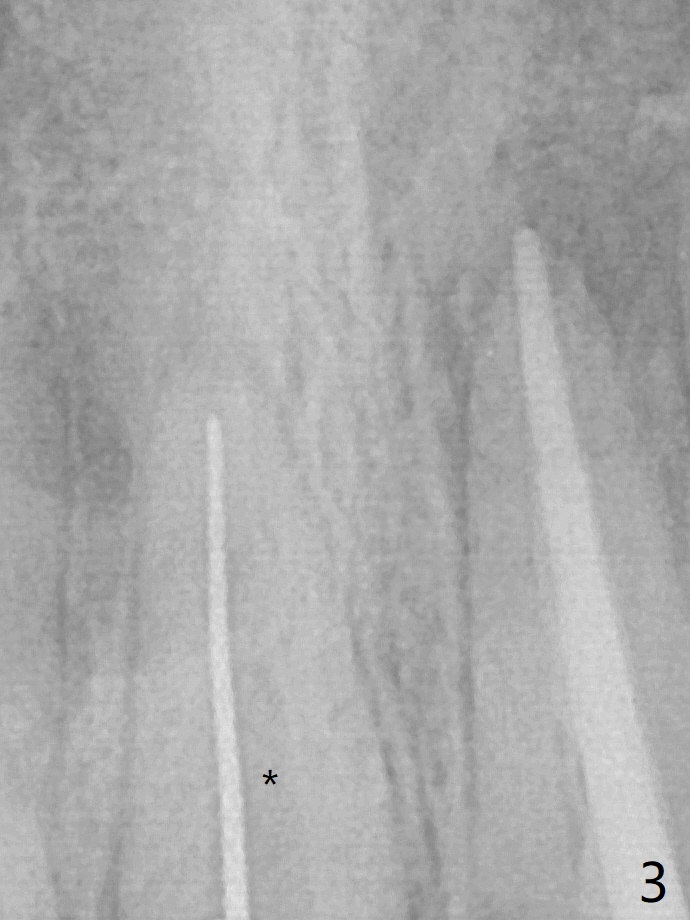

*:钙化(rotary file: 40/.04, 21.5 mm);P: 氢氧化钙糊剂。